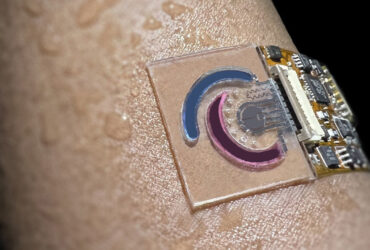

در این راستا، تیم پژوهشی دانشگاه علوم پزشکی تهران و همکاران بینالمللی موفق به ساخت پلیآمیدوآمین (PAMAM) مگامرهای قابل تغییر اندازه و بار (SChPMs) شدند که برای انتقال داروی دوکسوروبیسین طراحی شدهاند. این نانوحاملها با اتصال دندریمرهای PAMAM از طریق پیوندهای حساس به pH و پوشش PEG سطحی ساخته شدهاند. در محیط خنثی (pH 7.4)، اندازه و بار سطحی این ذرات حدود ۱۰۰ نانومتر و +۰.۷۵ میلیولت بود، اما در محیط اسیدی خارج سلولی تومورها (pH 6.5)، اندازه ذرات به ۱۵ نانومتر کاهش یافته و بار سطحی به +۶.۷ میلیولت افزایش یافت.

این تغییرات باعث شد نفوذ عمیقتر به تومورهای سهبعدی و جذب مؤثرتر توسط سلولها اتفاق بیفتد. به علاوه، نانوحاملها دارو را از غیر فعال شدن در محیط اسیدی خارج سلولی محافظت کرده و توانستند مقاومت سلولی نسبت به داروهای آنتراسیکلین را بهطور چشمگیری کاهش دهند. آزمایشهای حیوانی با استفاده از موشهای مبتلا به تومور ۴T1 نشان داد که این نانوحاملها فعالیت ضدتوموری قابل توجهی دارند و در عین حال کمترین آسیب بافتی را ایجاد میکنند.

پژوهشگران با تاکید بر اهمیت همکاری بین روشهای آزمایشگاهی و شبیهسازی مولکولی، اعلام کردند که طراحی این نانوحاملها نه تنها کارایی درمانی دارو را افزایش میدهد، بلکه میتواند مسیر توسعه فناوریهای بالینی مشابه برای درمان انواع سرطانها را هموار کند. علاوه بر این، تغییر اندازه و بار سطحی ذرات باعث افزایش فرآیند اندوسیتوز سلولی شده و نفوذ به نقاط عمیقتر تومور را تسهیل میکند.